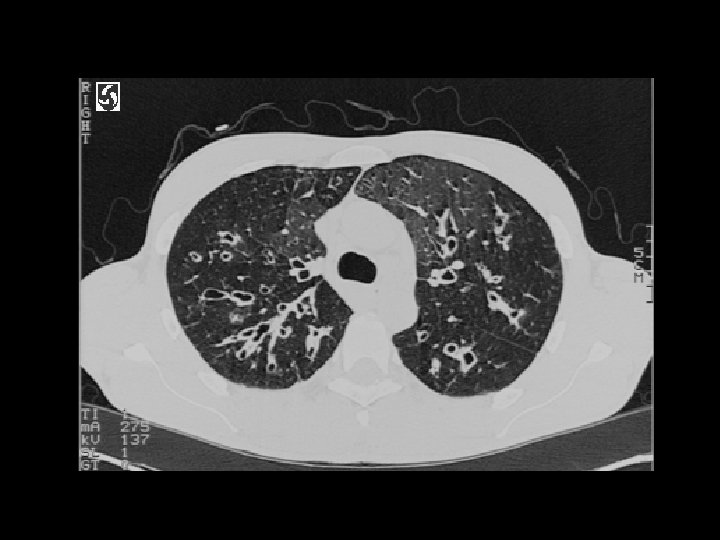

Cryptogenic organizing pneumonia (COP) • Findings: – patchy air-space consolidation in a predominantly peripheral and subpleural distribution • Unknown cause, assoc/w – connective tissue d/o – cocaine/drugs – HIV – MDS • ddx: – Chronic esosinophilic pneumonia – diffuse alveolar hemorrhage